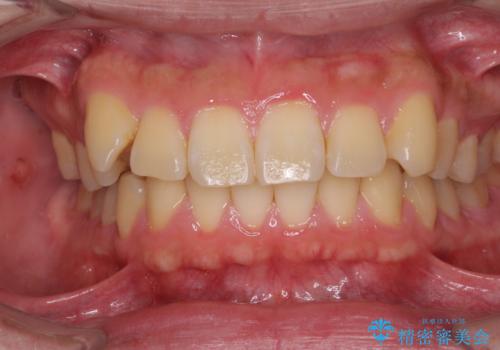

[前歯のねじれ・がたつきを治したい ]ワイヤーとマウスピースの併用矯正治療

![[前歯のねじれ・がたつきを治したい ]ワイヤーとマウスピースの併用矯正治療の症例 治療前](https://seimitsushinbi.jp/wp/wp-content/uploads/2023/11/IMG_0010-1-500x350.jpg?v=1699509973)

![[前歯のねじれ・がたつきを治したい ]ワイヤーとマウスピースの併用矯正治療の症例 治療後](https://seimitsushinbi.jp/wp/wp-content/uploads/2023/11/1c93ab7139a768f1f61b6dd35aac7324-500x350.jpg?v=1699510065)